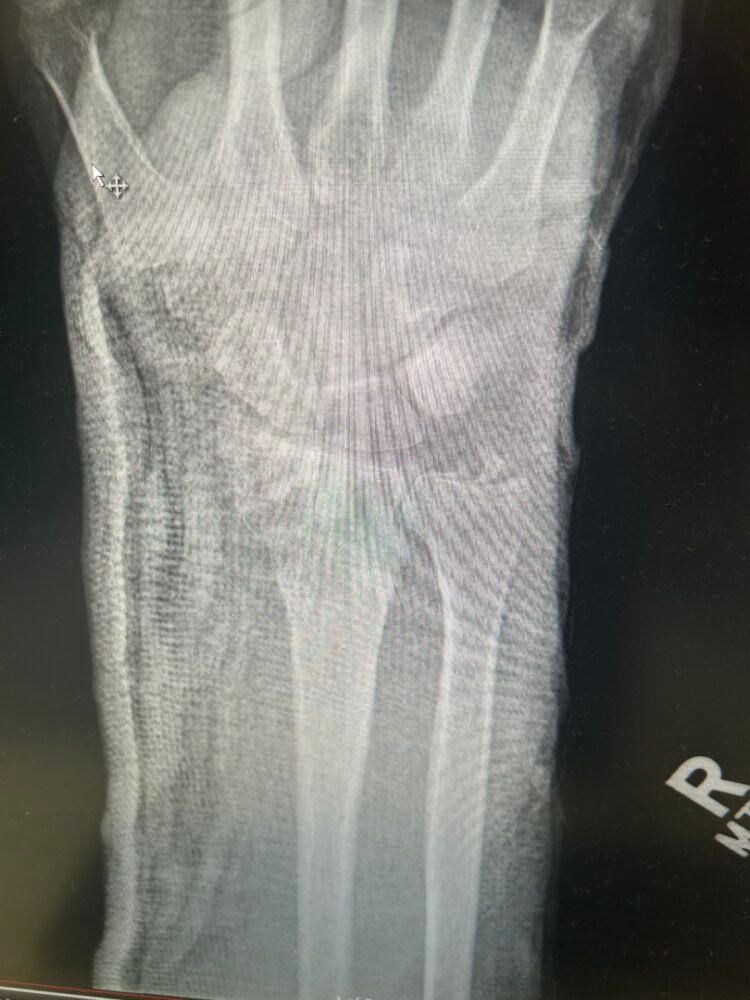

The title of this post mentions a glitch and that would be that I had a fall and broke my wrist quite badly and needed surgery to insert plates . This has meant that I have not been able to do any of the packing up and removal of the kitchen. It is extremely frustrating to say the least.